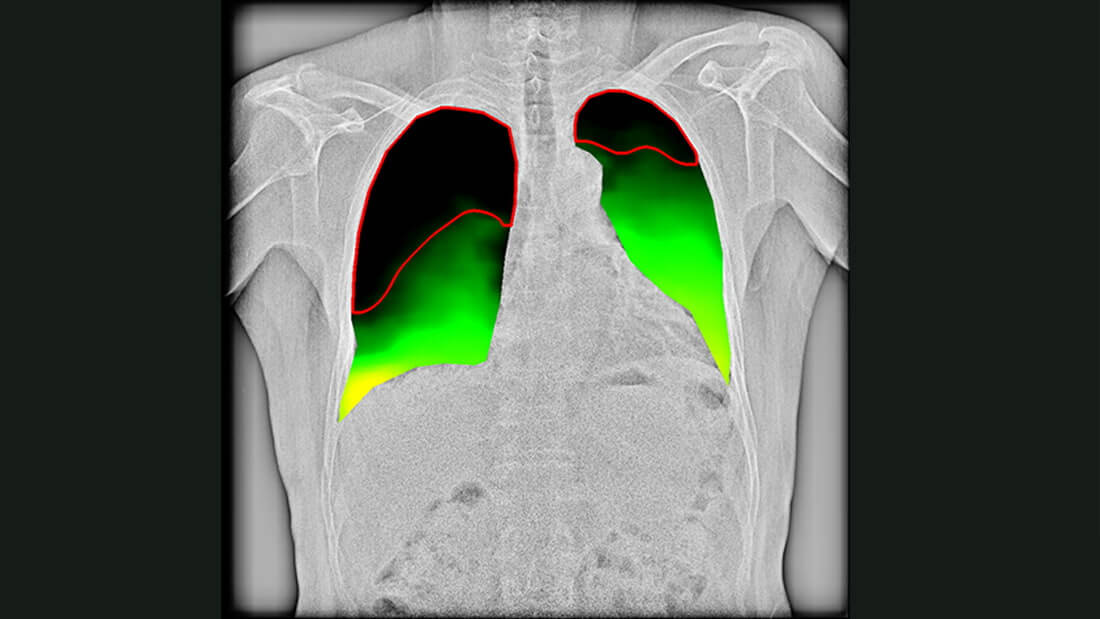

LM-MODE(サマリ画像)※

肺野内の⾎管影などを含む信号値パターンを追跡し、呼吸に伴う各領域の移動量を計測することにより、動きの傾向をカラー表⽰

※オプション機能

LM-MODE(ダイナミック画像)※

肺野内の血管影などを含む信号値パターンを追跡し、最大吸気位フレームを基準とした呼吸に伴う各領域の移動量をベクトル表示